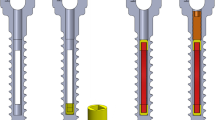

The basic body of a BISS screw is a cannulated spongiosa screw (titanium basic alloy, TiAl6V4), with a transducer coil being inserted into its hollow space. The cannulated screw (including screw head, shaft and thread face) is used as the first electrode. Subsequent to implanting the coil, the tip of the screw (without thread) is adapted as the second electrode, using an adhesive which is electrically isolating (epoxy resin, named Hysol, Dexter Co., USA) into the other part of the screw (Fig. 2). The BISS screw (GEOT, Germany) is available in different lengths and diameters. A size suitable for the treatment of necrosis of the femoral head was tested in the examinations relevant for this study. In a control group, cannulated spongiosa screws—the body of the BISS screws—with a length of 80 mm, an external diameter of 6.5 mm, a (tapping) spongiosa thread length of 44 mm, and a core diameter of 5 mm (manufactured by DePuy, UK) were used.

The new BISS system is based upon the technical foundations of the electroinduction method introduced by Kraus and Lechner [14] and Ascherl [1] (frequency 20 Hz, magnetic induction 5 mT, actual voltage 700 mV, internal resistance <100 Ω). Also in this context, extracorporeally applied electromagnetic alternating fields create a flow of current intracorporeally in the target tissue by way of the transformer principle. The successful utilisation of this principle in the context of bony tissue requires a reproducible application of the electrodes. By using the newer system, it is possible to reduce the parts to be implanted (Fig. 7), which results in a simpler application method and last but not least in a much easier way of removing the implants.